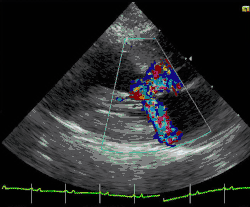

Depending on whether the distortion of normal heart anatomy causes an obstruction of the outflow of blood from the left ventricle of the heart, HCM can be classified as obstructive or non-obstructive.[35] The obstructive variant of HCM is hypertrophic obstructive cardiomyopathy (HOCM), also historically known as idiopathic hypertrophic subaortic stenosis (IHSS) or asymmetric septal hypertrophy (ASH).[36] The diagnosis of left ventricular outflow tract obstruction is usually made by echocardiographic assessment and is defined as a peak left ventricular outflow tract gradient of ≥ 30 mmHg.[35]

Clinically, cats with hypertrophic cardiomyopathy commonly have a systolic anterior motion (SAM) of the mitral valve (see graphic).[79] Cats with severe HCM often develop left heart failure (pulmonary edema; pleural effusion) because of severe diastolic dysfunction of the left ventricle. They may also develop a left atrial thrombus that embolizes, most commonly, to the terminal aorta creating acute pain and rear limb paralysis (see below). Sudden death can also occur but appears to be uncommon.[80][81]